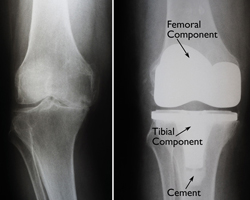

Total Knee Replacement